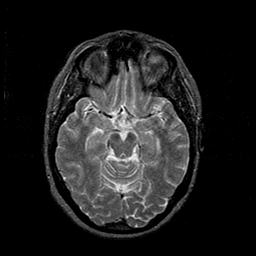

MR Study #1 -- Slice #22

[Home][Help][Clinical][Tour 1][Tour 2][Tour 3] Slice 22